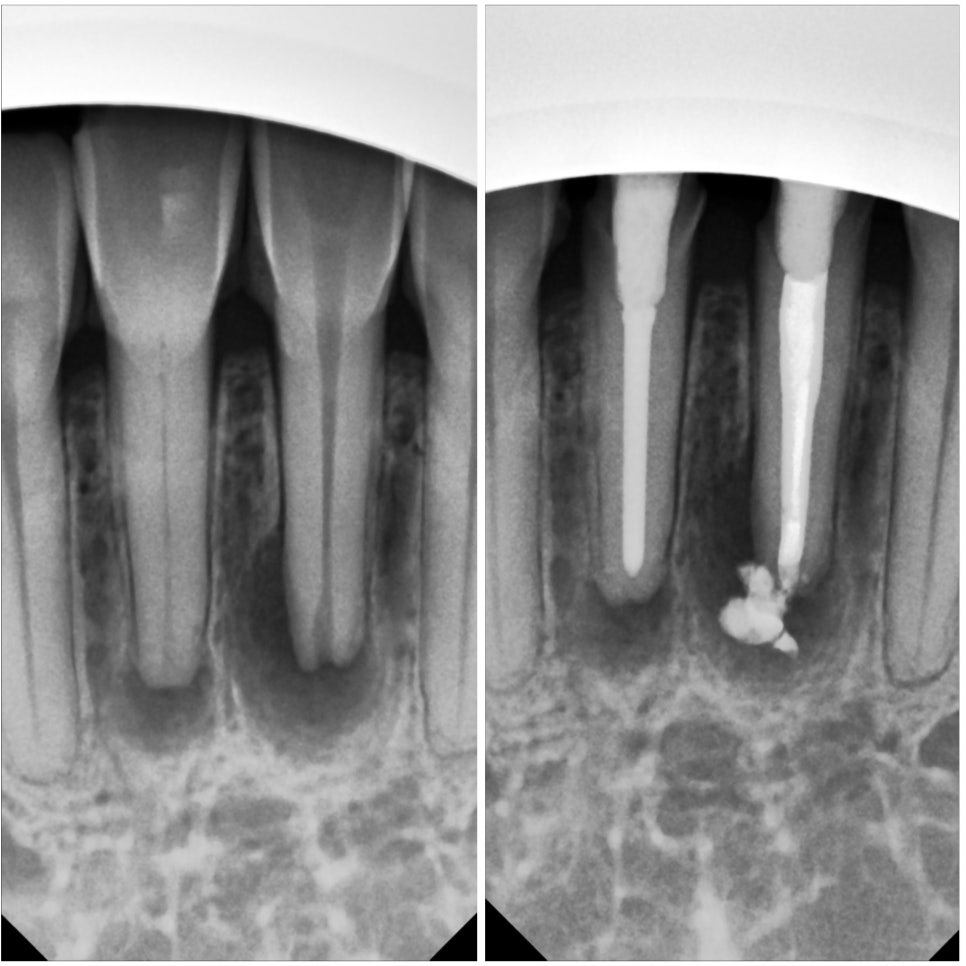

결국 이렇게 신경치료를 잘 마치기는 했지만,

정말 힘들었습니다.

보통 신경치료할 때는

저속으로 회전하는 전동 모터에

신경치료용 바늘을 끼워 사용하는데

저렇게 신경관이 넓으면

전동 모터를 사용할 수 없고

손으로 넣었다 뺐다 하는

철사같은 바늘을 사용해야합니다.

그거 하면 제 엄지 검지에 마찰이 상당해서

손에 열이나고 아프거든요 ㅠㅠ

정말 어렵게어렵게 치료했어요.

크라운 제작용 석고 모형

신경치료가 마무리 됐으면

그다음엔 이렇게

치아에 크라운을 씌울 수 있게

모양을 다듬어야 합니다.